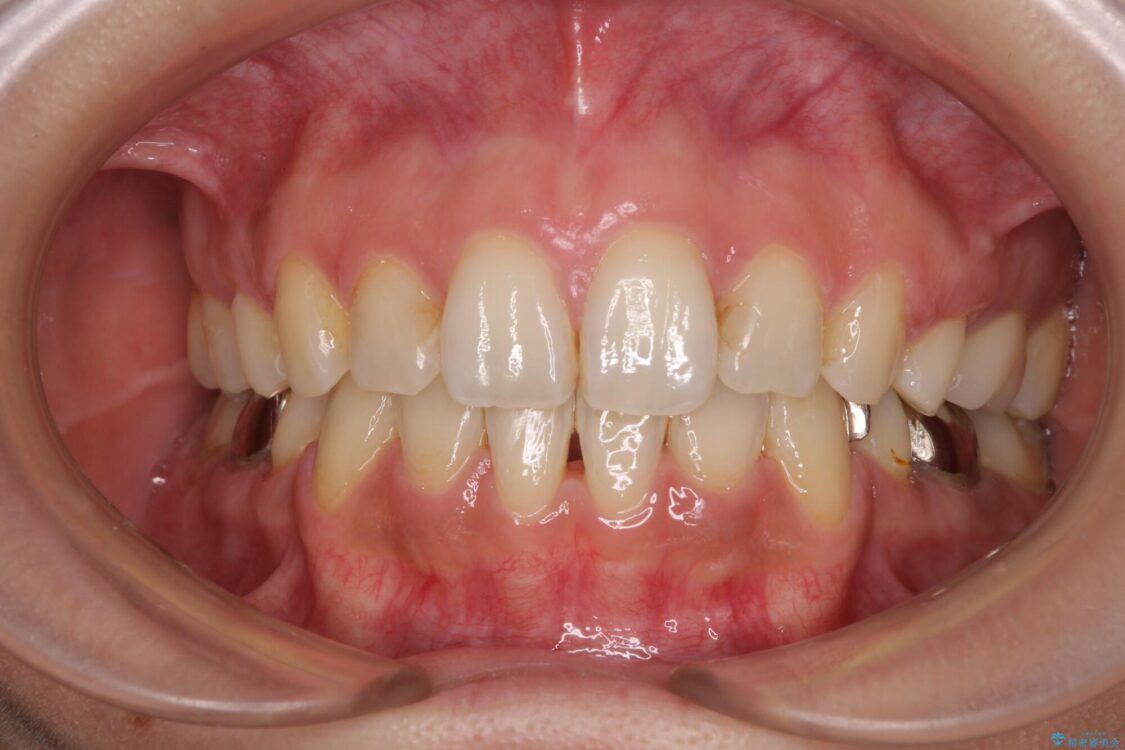

治療後

• デコボコと口元の突出感 ハーフリンガルでの抜歯矯正 治療後画像